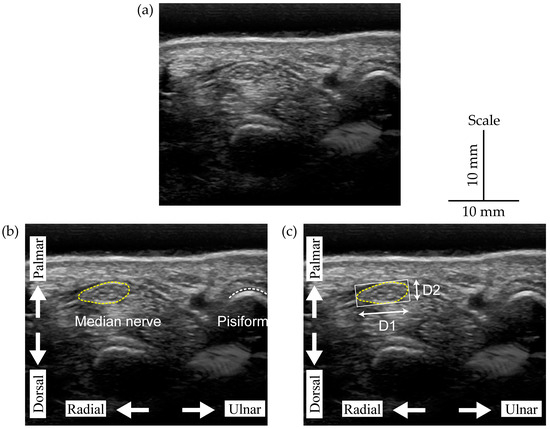

| Diameter (Longitudinal, D1) | rs (98) = 0.606, p < 0.001 | rs (98) = 0.317, p = 0.001 |

| Diameter (Vertical, D2) | rs (98) = 0.440, p < 0.001 | rs (98) = 0.061, p = 0.546 |